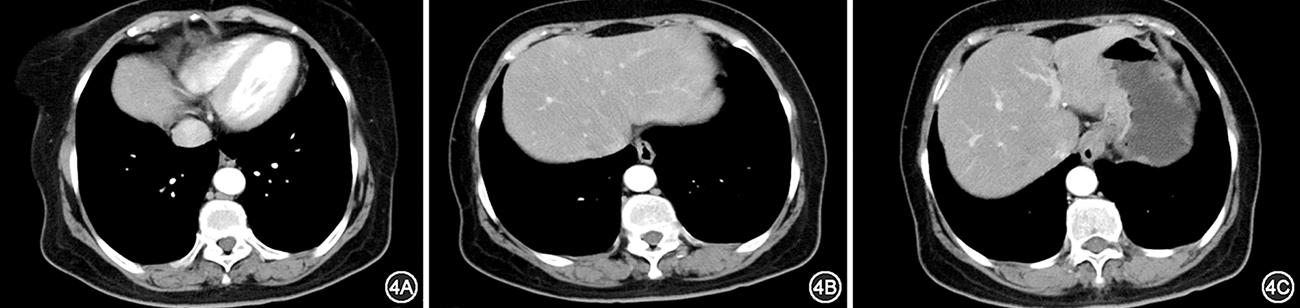

图4

Ⅰ型(图2)肿瘤上界位于C层面以下。2A:C层面(未见肿瘤上界),2B:C层面以下(出现肿瘤上界)。Ⅱ型(图3)肿瘤上界位于B和C层面之间。3A:B层面(未见肿瘤上界),3B:B和C层面之间(出现肿瘤上界)。Ⅲ型(图4)肿瘤上界位于A和B层面之间。4A:A层面(未见肿瘤上界),4B:A和B层面之间(出现肿瘤上界),4C:B层面(可见肿瘤瘤体)。Ⅳ型(图5)肿瘤上界位于A层面以上。5A:主动脉弓层面(未见肿瘤上界),5B:A层面以上(可见肿瘤上界),5C:A层面(可见肿瘤瘤体)。